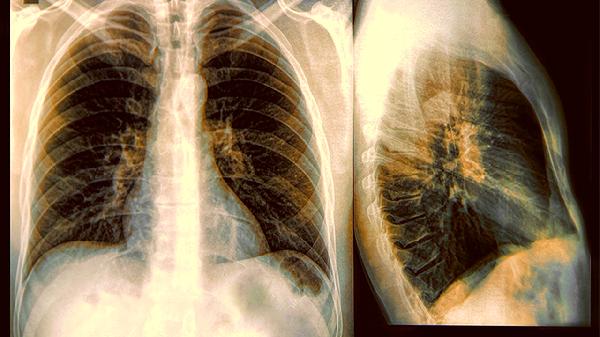

约30%的变异性哮喘患者肺功能检查结果正常,需依赖支气管激发试验确诊。其症状与慢性支气管炎、胃食管反流等疾病高度相似,易被误诊。咳嗽变异性哮喘患者甚至可能被长期当作普通感冒治疗,延误最佳干预时机。